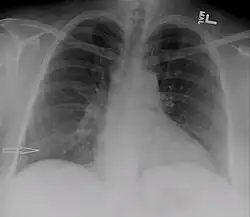

| Right sided pleural effusion caused by urinothorax | |

Urinothorax (pl. urinothoraces) is defined as urine in the fluid-filled cavity that surrounds the lungs.[1] It is usually caused by obstructive uropathy. It is mainly diagnosed by analyzing the pleural fluid. Treatment involves treating the underlying condition, which typically results in resolution of the urinothorax. It is an extremely rare cause of pleural effusion.[2]

The characteristics of people affected by urinothorax are poorly defined. Urological symptoms tend to occur, while the respiratory symptoms are typically nonexistent or mild.[3] Difficulty breathing, occurring in moderate to large pleural effusions, is the most common respiratory symptom.[4] Other symptoms include fever, abdominal pain, chest pain, and reduced urination.[3] It typically occurs within hours of the causative condition.[5]